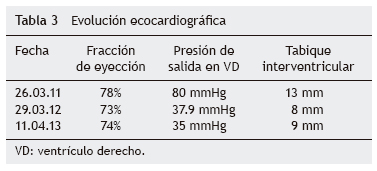

Hacia el quinto mes mejoró la movilidad, con desplazamiento gateando y con arrastre. El ecocardiograma registró franca mejoría en grosor de septum y pared ventricular. Al finalizar el semestre de TRE, hubo clara mejoría en la postura de la espalda, mejor esfuerzo respiratorio y ausencia de fatiga. Se intercalaron 2 horas de oxígeno inhalado con 2 horas de BiPAP. La paciente mostró mejor tono muscular en las piernas. Se alternaron 3 horas de BiPAP con 3 horas de oxígeno con puntas nasales. Dormía con BiPAP. Ante la evidencia de mejoría de la hipertensión pulmonar se decidió suspender el tratamiento con sildenafil y furosemida, vigilando de forma estrecha cualquier dato de recaída.

Al cumplirse el primer año de TRE se realizó ecocardiograma que mostró disminución del grosor del septum interventricular (8 mm), PSVD de 35 mmHg y función sistólica del mismo VD conservada, con fracción de eyección del 74% y fracción de acortamiento del 42% (tabla 3).

La EP tiene un amplio espectro clínico al derivar del depósito de glucógeno en tejido muscular y visceral. Es evidente que la función cardiaca en la variante de inicio temprano presenta un extremo compromiso, pero se pueden obtener resultados satisfactorios con TRE, logrando una remodelación del miocardio y de la función ventricular, así como disminución del grosor de la pared ventricular. En EP tardía, por lo general, se describe la afección cardiaca como poco frecuente o menos grave, y los resultados de TRE en relación con la función cardiaca han sido desalentadores y no se ha descrito mejoría en la función o en el tamaño ventricular. En este caso clínico existe evidente afectación del músculo cardiaco, así como insuficiencia cardiaca al inicio de la enfermedad (como se mostró en el ecocardiograma) con hipertrofia de ventrículo derecho e hipertensión pulmonar, documentándose además presión de salida del VD de hasta 80 mmHg. A diferencia de los informes que existen en la literatura, donde no se registra un cambio significativo en la función ventricular o en el grosor de la pared entre pacientes con EP tardía, la evolución de esta paciente demostró que la TRE puede lograr una disminución significativa de la presión de salida de VD, de 80 mmHg hasta 35 mmHg. Asimismo, se documenta una disminución en el grosor inicial del tabique interventricular, de 13 mm a 9 mm. Con la reversión de la insuficiencia cardiaca, se suspendió el tratamiento anticongestivo y vasodilatador.